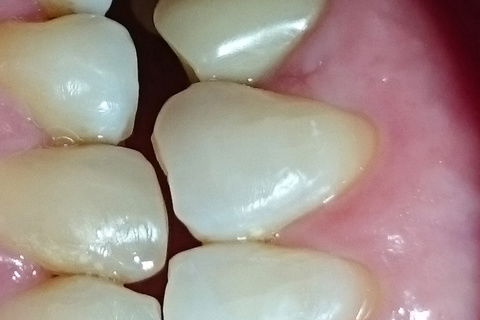

Tecido de revestimento 5 meses após enxerto gengival livre

Codicionamento gengival 60 dias após reabertura.